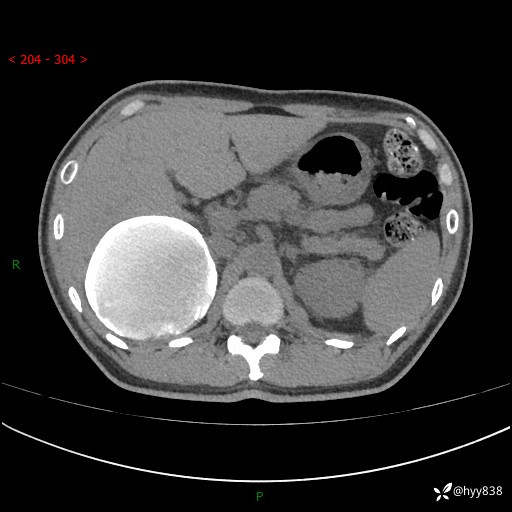

性别:男

年龄:50岁

简要病史:夜尿增多半月,发现肾功能异常1天,超声发现腹膜后占位

腹部CT平扫+增强